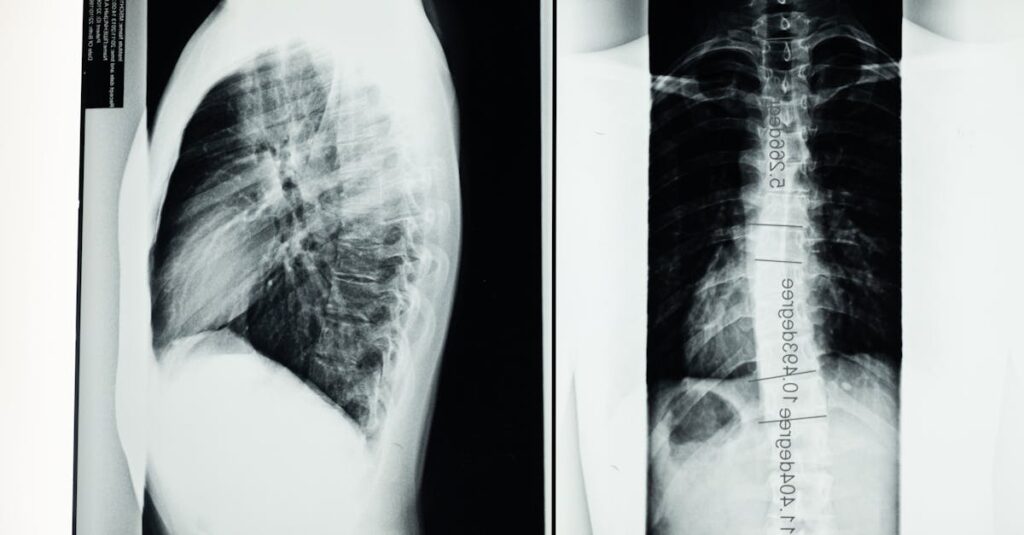

Qu’est-ce qu’une hernie discale?

Une hernie discale est une condition où le noyau d’un disque intervertébral se déplace et exerce une pression sur les nerfs environnants, causant douleur et inconfort.